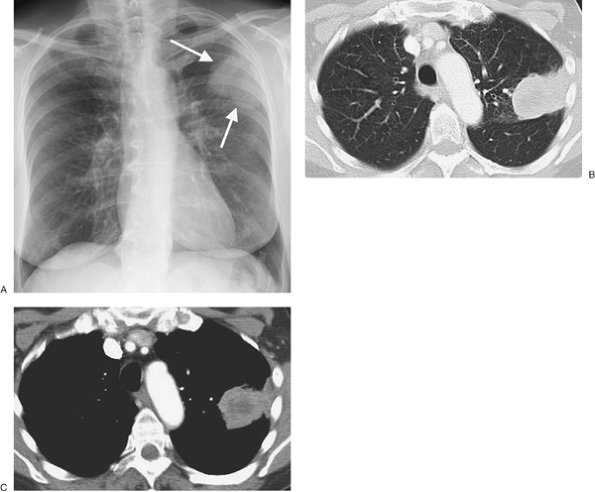

The phrenic nerves, which arise from the third through fifth cervical nerves, supply the diaphragm (“C3, 4, 5 keep the diaphragm alive”). The right phrenic nerve descends at the right side of the superior vena cava and right atrium, in front of the

P.161

P.162

root of the right lung, between the pericardium and mediastinal pleura. The left phrenic nerve descends between the left subclavian and left common carotid arteries, lateral to the vagus nerve and the arch of the aorta. It passes in front of the root of the left lung between the mediastinal pleura and the pericardium, and its branches pierce the diaphragm immediately to the left of the pericardium. Tumor invading the phrenic nerve on either side can result in elevation of the ipsilateral diaphragm and should always be considered as the cause of an abnormally elevated diaphragm in patients over age 35 unless proven to be stable for 2 years or more on prior chest radiographs (Fig. 9-44). The chest radiograph may not show the tumor itself, and occasionally the elevated diaphragm may be the only radiographic clue to an underlying neoplasm.

FIGURE 9-44. Bronchogenic carcinoma invading the phrenic nerve. A: PA chest radiograph of a 74-year-old woman shows normal positioning of the hemidiaphragms. B: PA chest radiograph obtained 1 year later shows elevation of the right hemidiaphragm and no evidence of mediastinal mass. C: CT shows a homogeneous soft tissue mass adjacent to the superior vena cava (arrows), which proved to be a bronchogenic adenocarcinoma invading the right phrenic nerve. This case illustrates the significance of new diaphragmatic elevation in an adult, even when no mediastinal mass is seen on the chest radiograph.